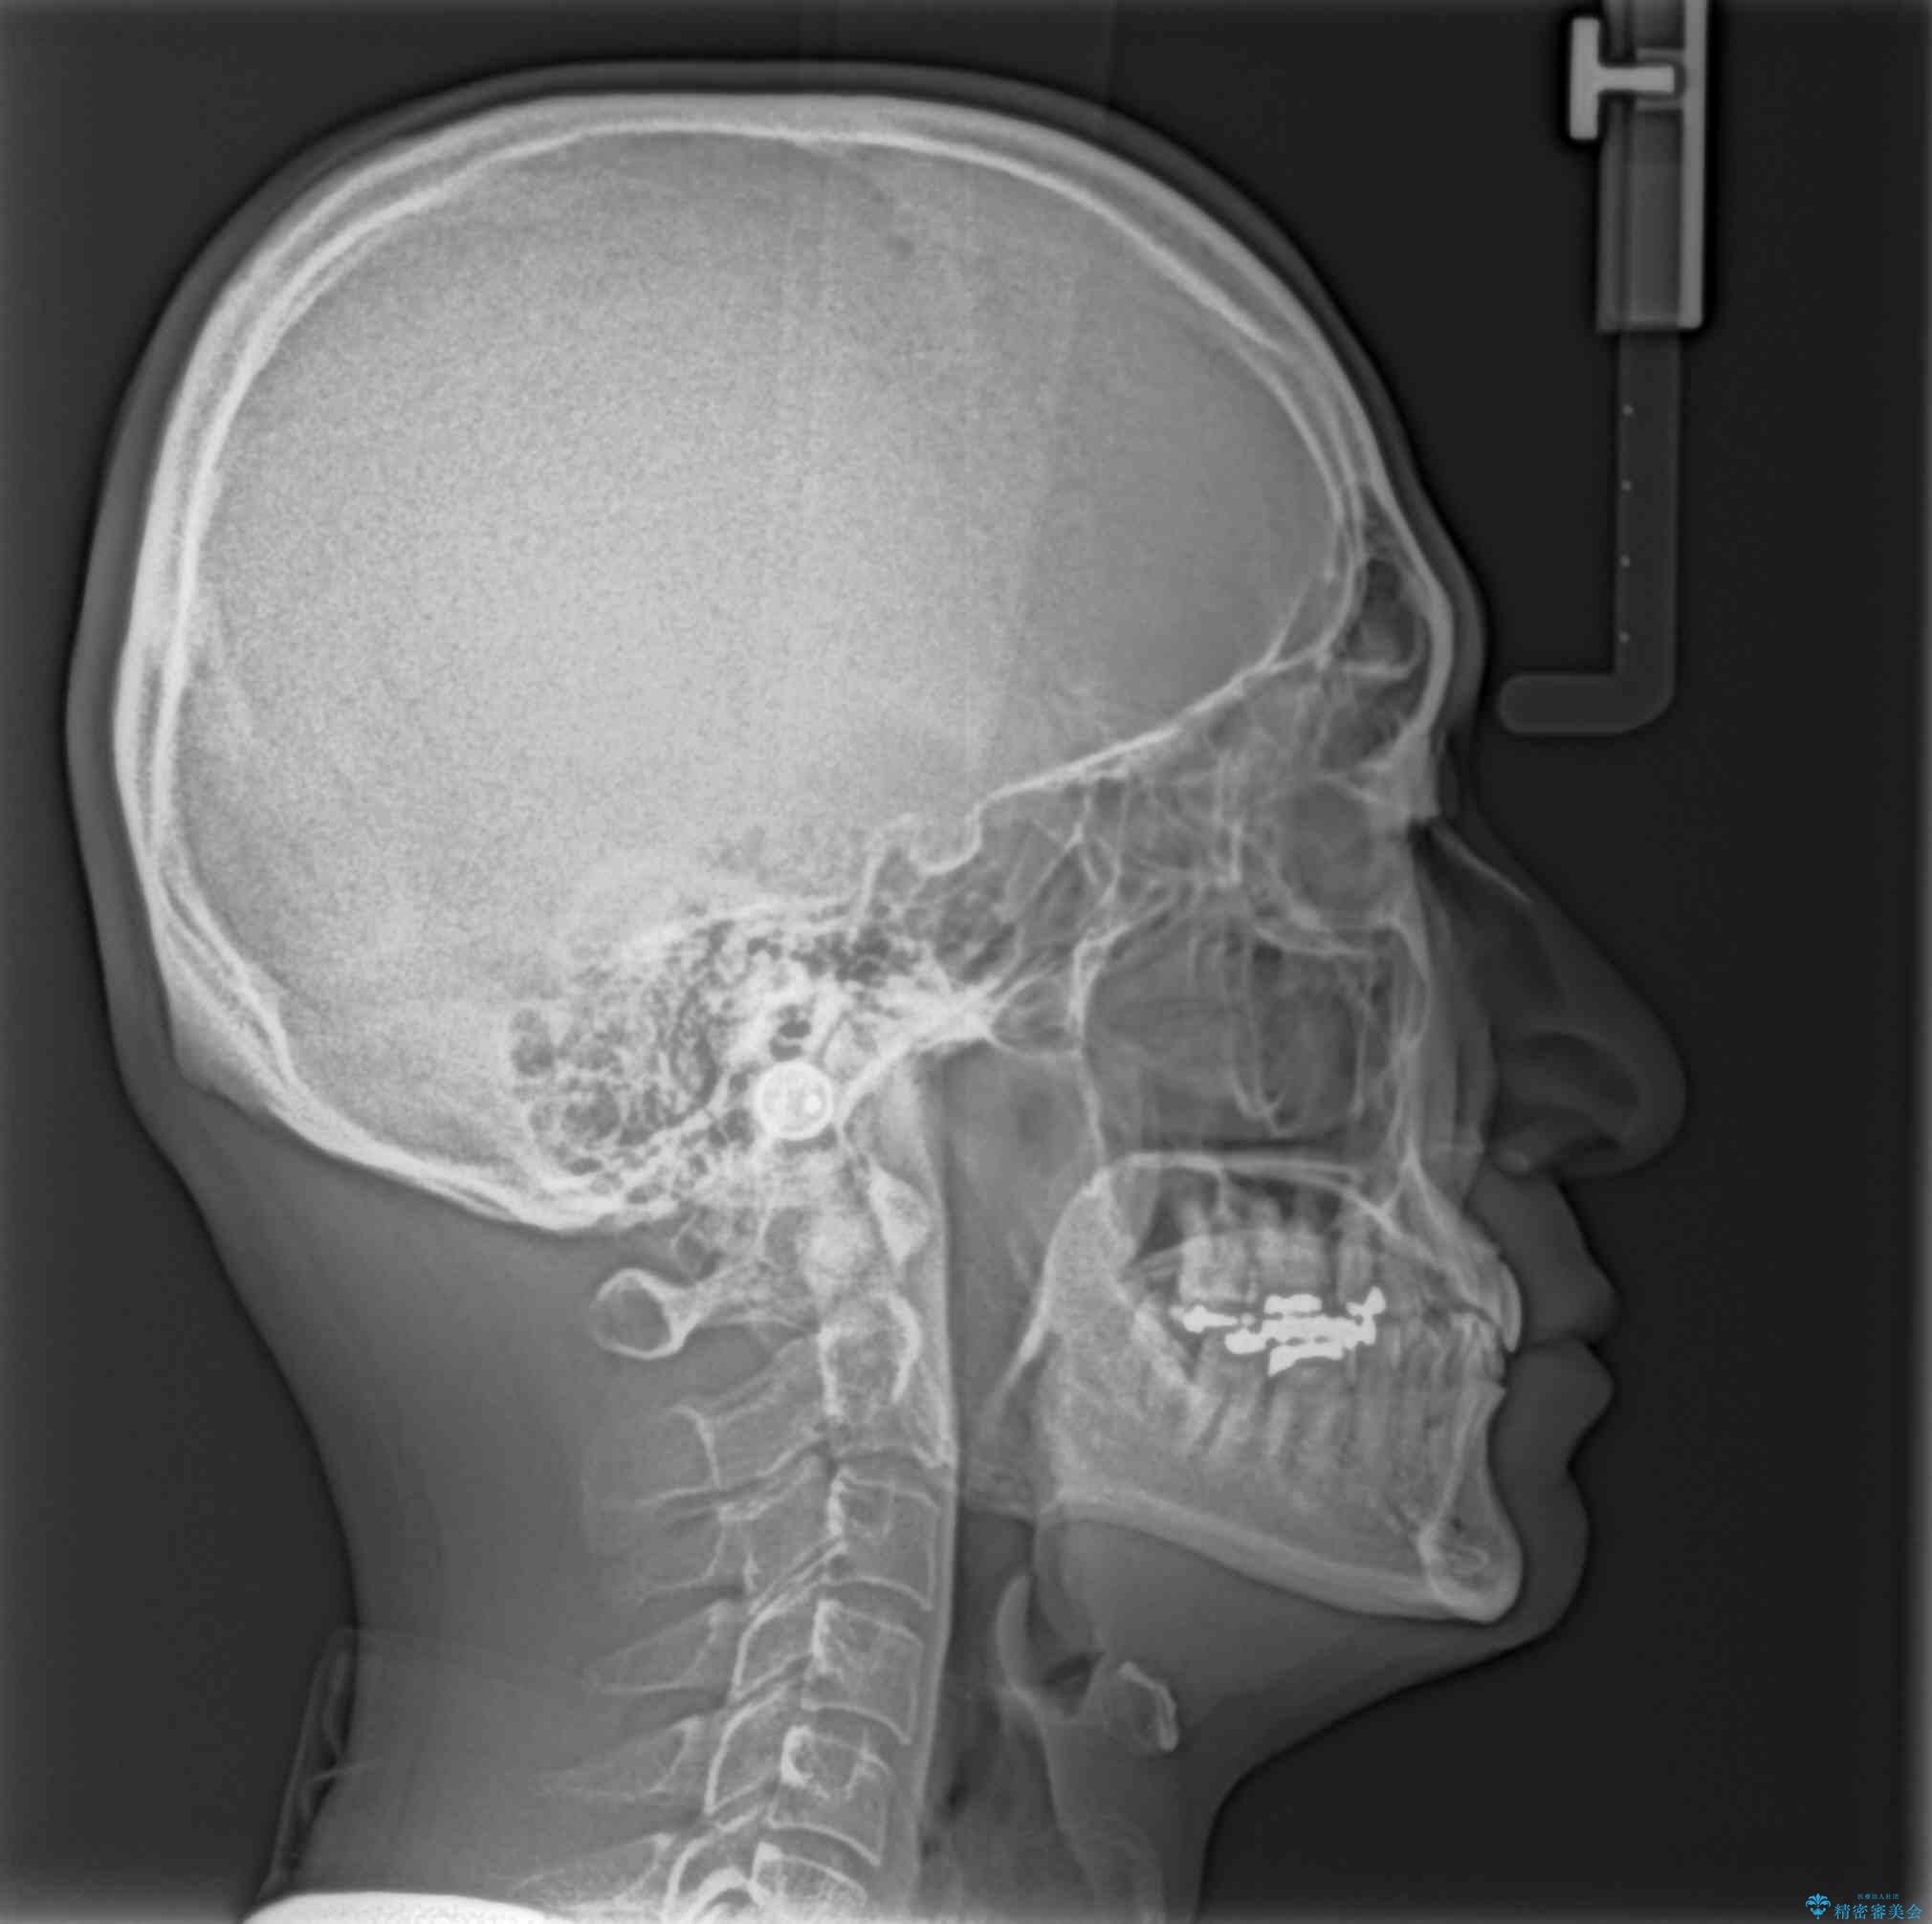

下顎前歯が隠れるほどのディープバイトにより、強い咬合力と突き上げで上顎歯列に隙間が空いている状態でした。

手前に傾斜している奥歯をワイヤー装置で立ち上がらせ、咬み合わせの高さを挙上することで突き上げを解消し、空隙歯列を改善していくこととしました。

ディープバイトが改善され、睡眠時の食いしばりも緩和され、顎への負担が軽減されました。